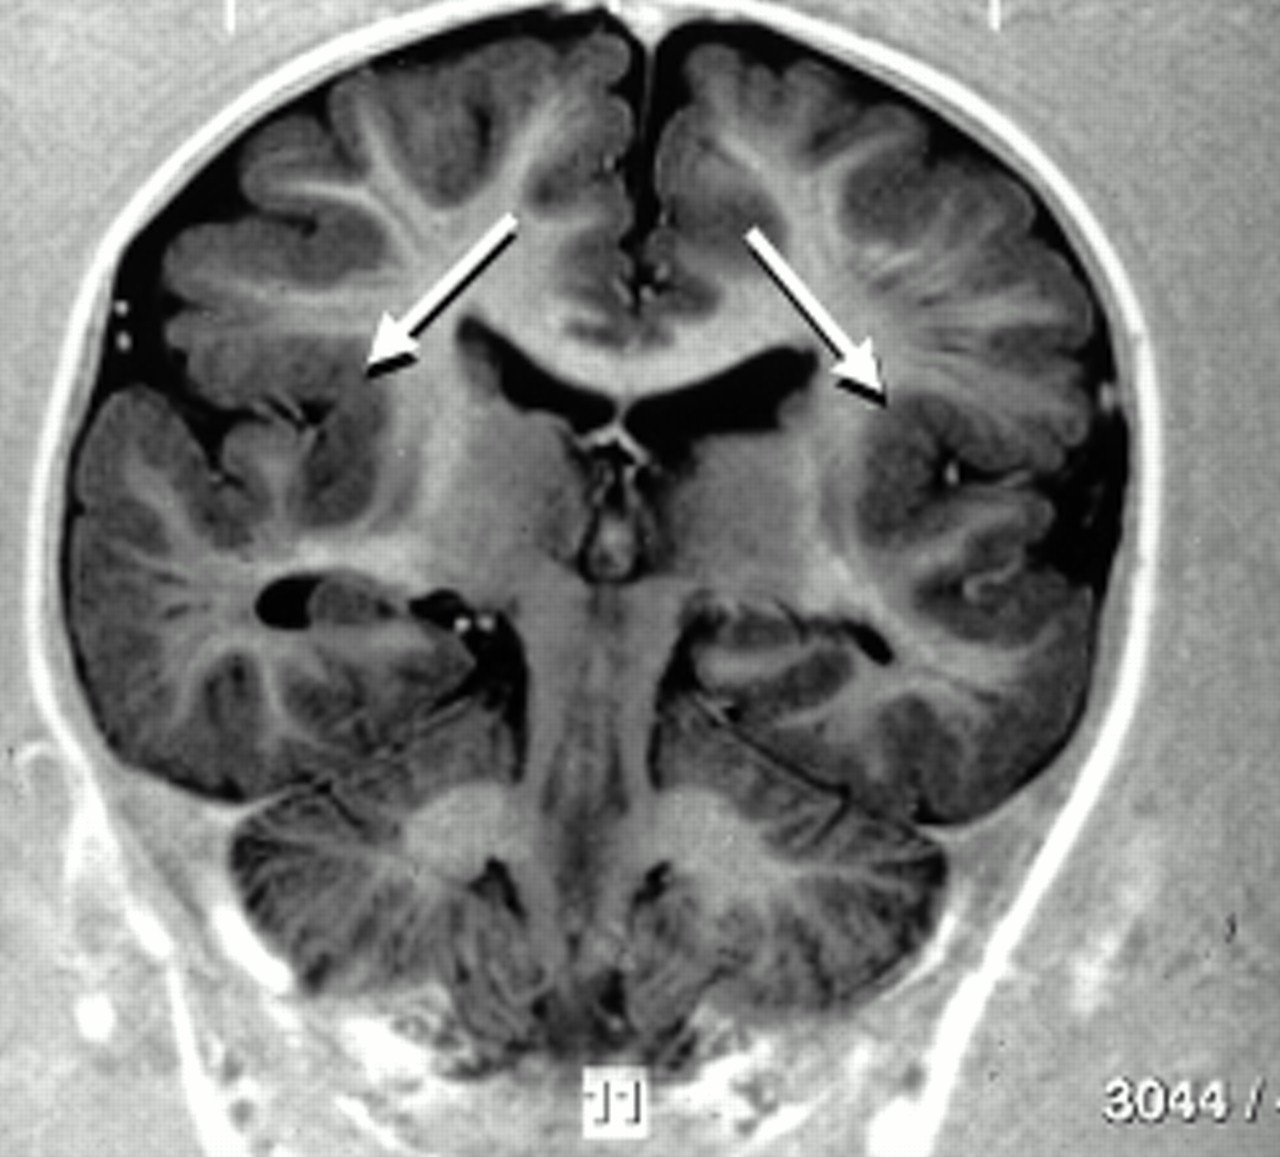

Pachygyria

“Thick Gyri”